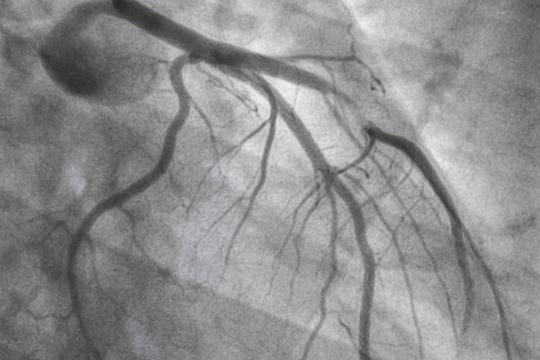

PCI

A prospective registry that represents a regional collaborative effort to assess and improve quality of care and outcomes of patients undergoing percutaneous coronary intervention.